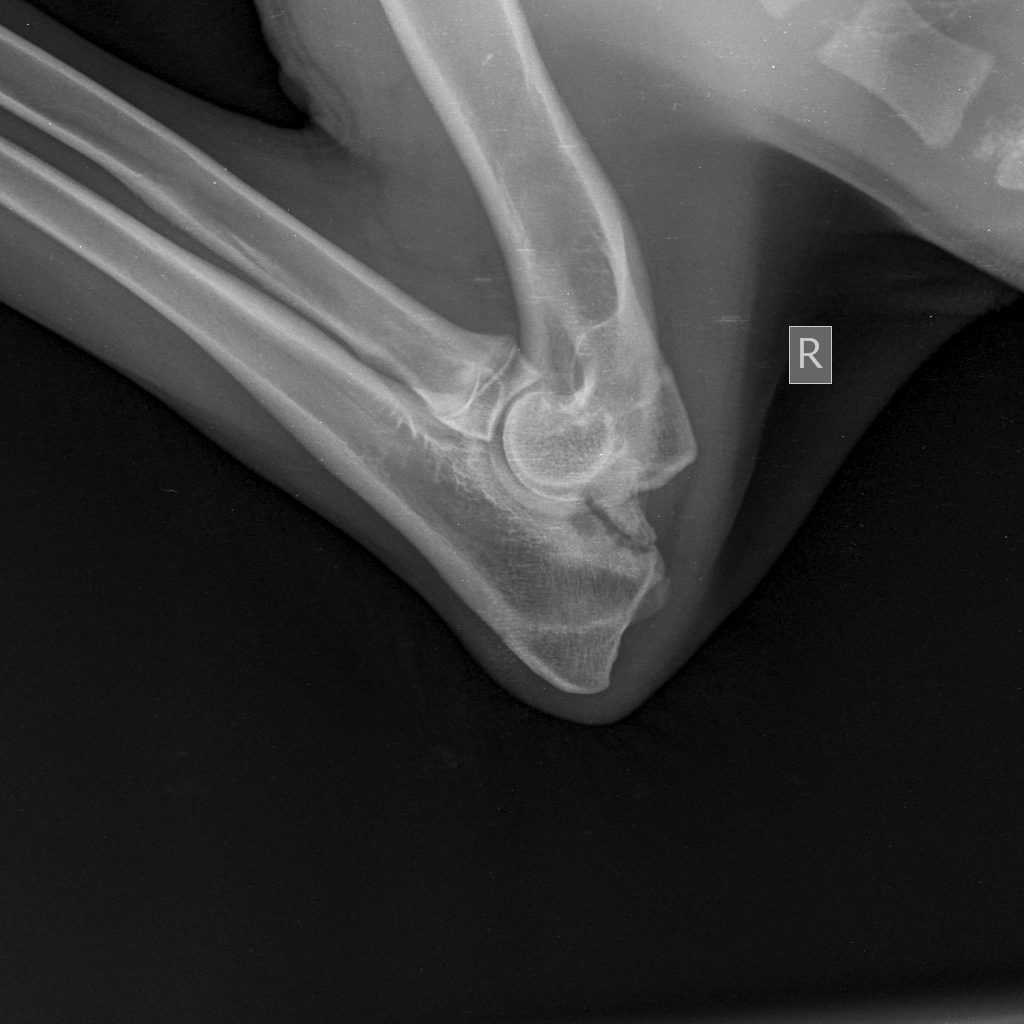

Как производится диагностика дисплазии локтевых суставов?

На ранних стадиях заболевания сложно поставить диагноз при помощи рентгеновских снимков. Необходимо исследовать оба локтя. Для этого делают рентгеновские снимки в следующих проекциях:

- Медиолатеральная проекция разогнутого локтя;

- Медиолатеральная проекция согнутого локтя;

- Краниокаудальная проекция;

- Краниолатеральная-каудомедиальные наклонные проекции для очерчивания медиального венечного отростка (при необходимости).

Рентгенография проводится без седации животного. Это совершенно безболезненная процедура, занимающая всего несколько минут времени, но дающая колоссальную информативность о состоянии суставов.